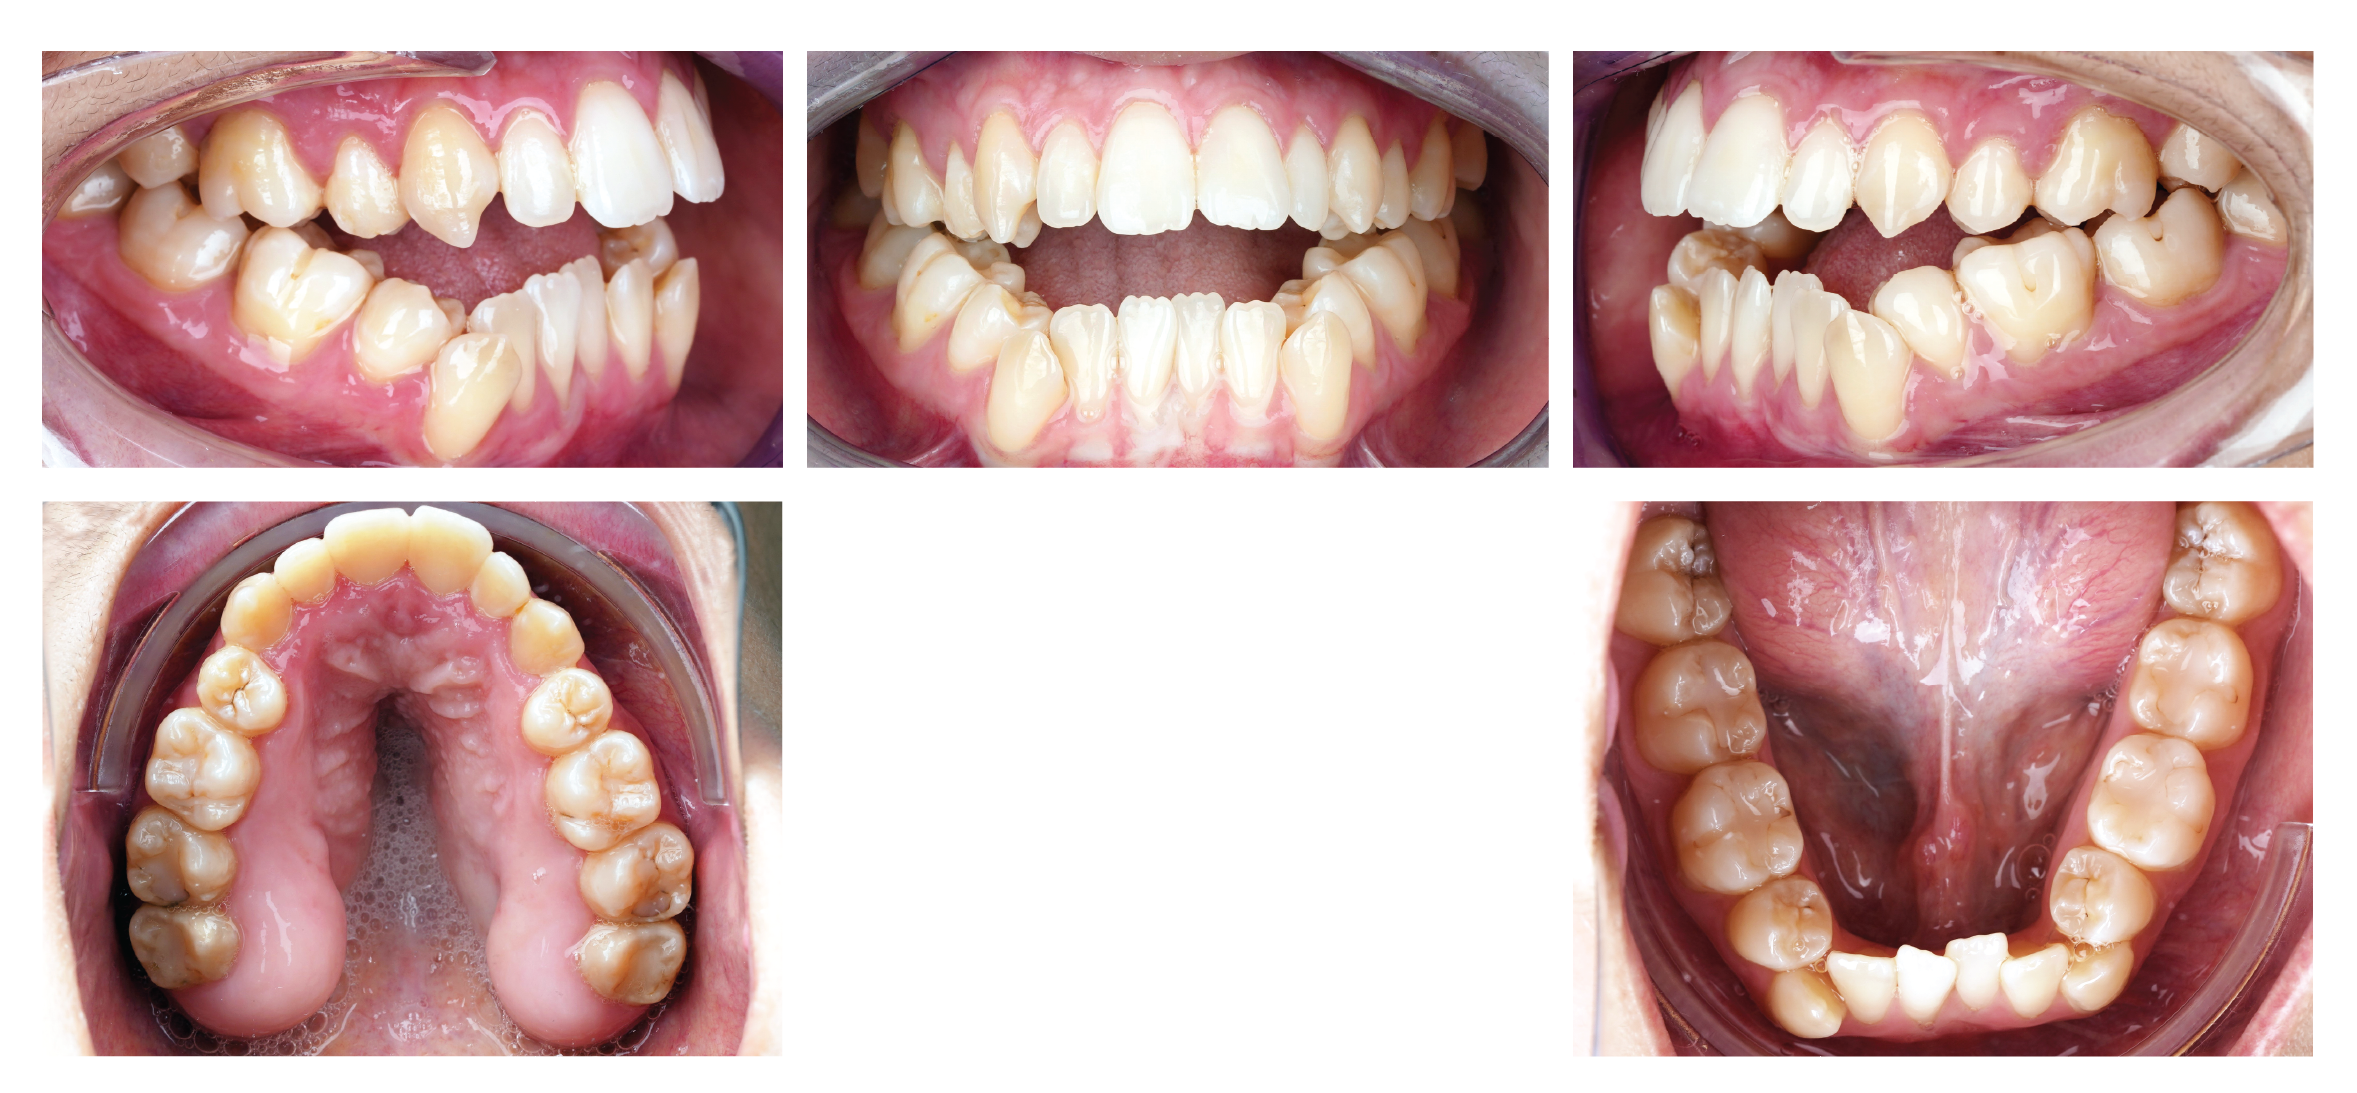

Figure 1: Intra-oral manifestation of a patient with Nemaline Myopathy. Intraoral images of the patient demonstrated severe open bite, severe retroclination of mandibular anterior teeth, severe crowding in the lower arch, severe overjet, and divergent upper and lower occlusal planes.